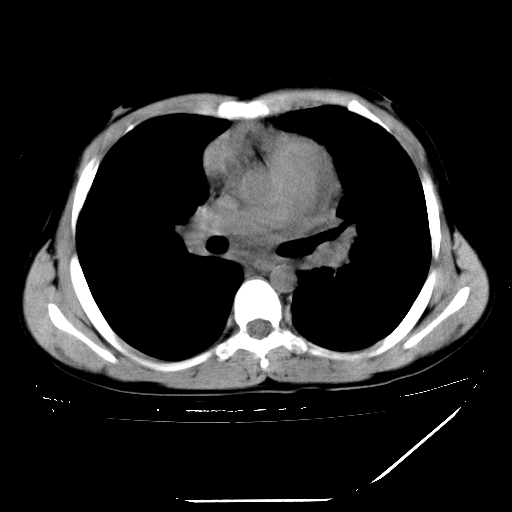

男,13岁,咳嗽、咳痰伴发热一周。

上纵隔课件多枚淋巴结,部分相互融合,左侧支气管壁增厚,肺纹理较右侧增粗,患者,男,13岁,

中上纵隔见多枚淋巴结肿大,部分相互融合成团片,左肺门增大,上叶支气管变窄,肺内多处斑片状 索条状及棉絮状致密影。临床“男,13岁,咳嗽、咳痰伴发热一周。”首先考虑:原发综合征!不除外淋巴瘤可能!

纵隔多发肿大淋巴结,部份有融合改变。双肺血管气管束增厚,以肺门为中心向外周散发,以左肺下叶为明显。考虑淋巴瘤可能性大。不除外原发综合征。

中上纵隔见多枚淋巴结肿大,部分相互融合成团片,左肺门增大,上叶支气管变窄,左肺支气管血管束增粗,可见磨玻璃样影。临床“男,13岁,咳嗽、咳痰伴发热一周。”首先考虑:淋巴瘤可能性大!

中上纵隔见多枚淋巴结肿大,部分相互融合成团片,纵隔内脂肪间隙模糊,左肺门增大,上叶支气管变窄,左肺支气管血管束增粗,可见磨玻璃样影。考虑纵隔淋巴管炎